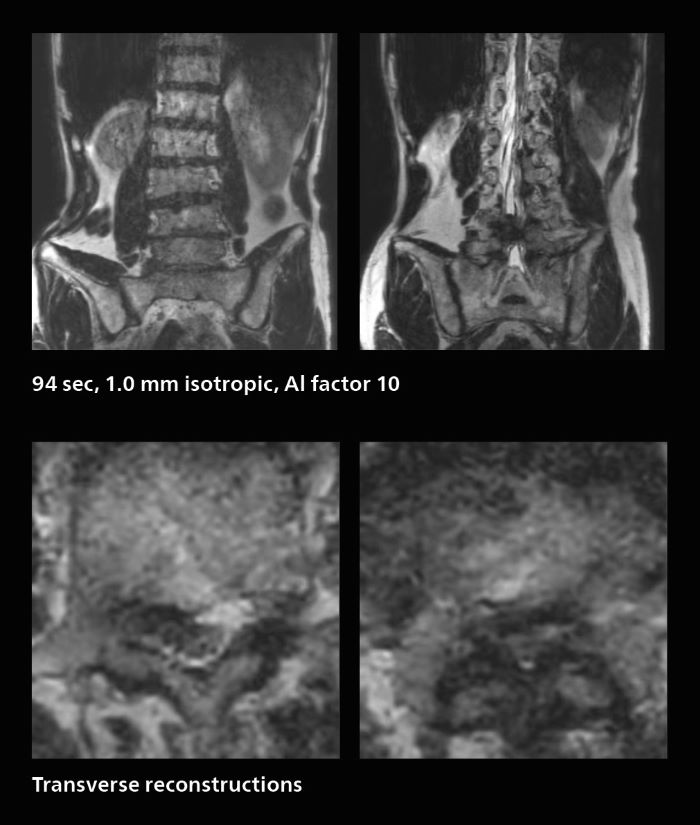

Faster lumbar spine exams are beneficial for patients with pain

Many patients who must undergo a lumbar spine examination suffer from back pain. For these patients it is difficult to maintain the imaging position long enough to successfully complete the examination. “In such cases, using SmartSpeed allows us to perform volume imaging, so that we acquire only one high resolution 3D sequence in a short time and then reconstruct the other orientations from that,” Dr. Katahira says. “This is highly advantageous because the patient needs only endure a short exam time, whereas before it was necessary to acquire a larger number of sequences in total. We have seen that the shorter time has allowed us to scan patients who previously could not finish the exam. This is a great advantage.”

Fast lumbar spine imaging for successful exam of patient in pain

A patient arrived saying that undergoing MRI was not possible because of severe back pain and leg pain, was imaged with SmartSpeed in only 94 seconds. The scan was diagnostic and afterwards the patient confirmed that it only took a little while. Performed on Elition X.

The hospital’s fast lumbar spine ExamCard includes T2W SpineVIEW, 1:40 min, 1.0 mm isotropic, acceleration factor 12.